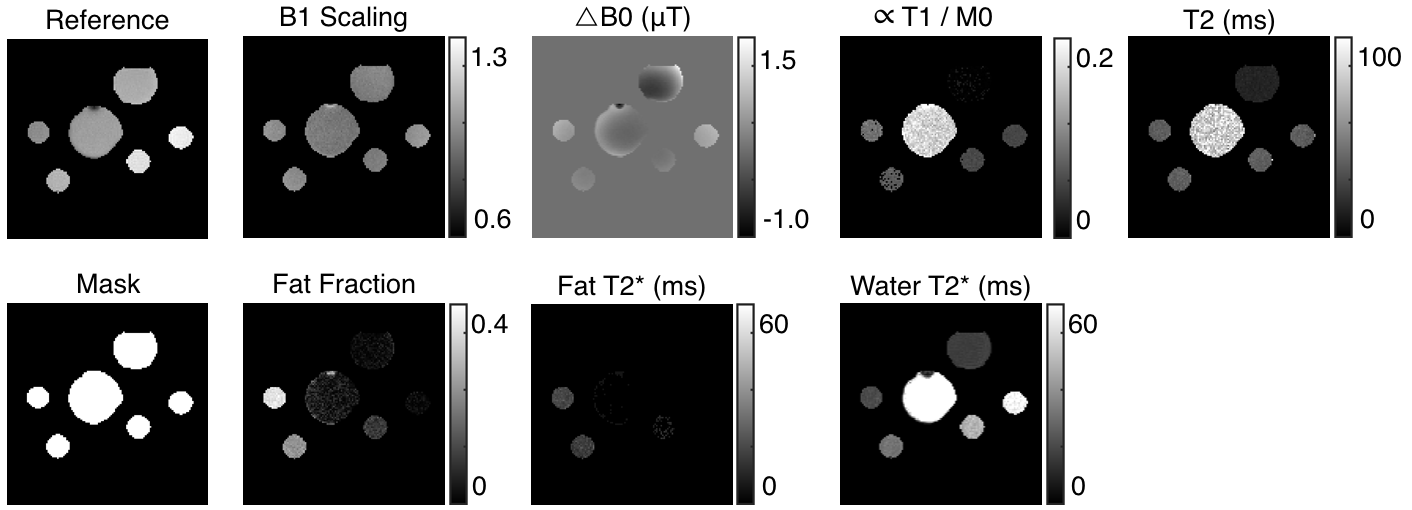

A binary mask is created using using the average image (an example is shown in Fig. 4) over all 22 images from the two segments using close and erosion morphological operations, similar to the methods presented in [11, 12]. Only those pixels indicated as having signal (white pixels in the mask) are processed in order to reduce the total computation time.

Once the map is estimated, an average corrected image can be computed from all of the acquisitions. This image can be used as an anatomical reference, and is presented in the results section as such.

Figure 4 shows the quantitative values estimated from the data of Fig. 3 using the methods described in section 2.2. The bright regions in the fat fraction map for bottles , , and are due to regions of the mask that exceed the actual data. Note that the fat fraction of bottles , , and are all approximately , as expected.

It is not expected that the fraction of signal due to fat equals the fat fraction volume (due to differences in the molar mass, differences in the number of hydrogen atoms per mole, and the chemical shielding of the fat molecule). However, it is expected that the fraction of signal due to fat is proportional to the percentage of fat in the voxel. We verify this in the fat fraction of the bottles estimated by comparing the ratios of different bottles as shown in Table 2. The ratio of signal intensities is approximately equal to the ratio of fat fraction per volume. This validates the fat fraction estimate attained by multiMap.

We present the estimates of , , and attained with multiMap to those of standard scanning methods in Fig. 5. Data was collected for each standard quantification individually. A double angle mapping sequence was used to measure B1 [7]. An exponential decay was fit to a series of data collected from a spin-echo sequence with different echo times to estimate . A five-parameter model was fit to data from an inversion recovery sequence according to [17] in order to estimate . The figure shows good agreement for each quantity. The estimate of of bottle is lower than the true value; this is due to the small length of time of the imaging pulse and the acquisitions , , and . In order to estimate longer values, one would need to spread out the acquisitions; this would come at a cost of reduced fidelity for smaller estimates.

For imaging the knee, the multiMap sequence used had a TR of ms and a of ms. The mask accurately isolates those pixels corresponding to tissue. Under the assumption that was long enough to accurately distinguish estimates of and , we also presented imagery. The fat and muscle show different values, as expected. The quantity in the cortical bone is high due to the short leading to a near signal in this region in image . The fat fraction shows increased signal intensity in the fat and bone marrow, as expected.

For imaging the brain, the multiMap sequence used had a TR of ms and a of ms. The mask accurately isolates those pixels corresponding to tissue. The map accurately depicts similar proton density in brain parenchyma, and the ventricles and top of the brain stem show darker regions. The map accurately depicts higher values in the ventricles. The fat fraction map accurately identifies that the fat is largely isolated to subcutaneous tissue. The ring of speckle in the fat fraction map (pointed to by the cyan arrow) results from the low signal intensity of bone. The of water, mostly saturated, shows that this quantity is outside the estimable range by the multiMap sequence used do to the small time difference between the saturation pulse and image . To estimate larger values, one would need to either add additional images after the saturation pulse but before the first probing pulse or spread images to a longer times (this would come at a reduced fidelity of smaller estimates.